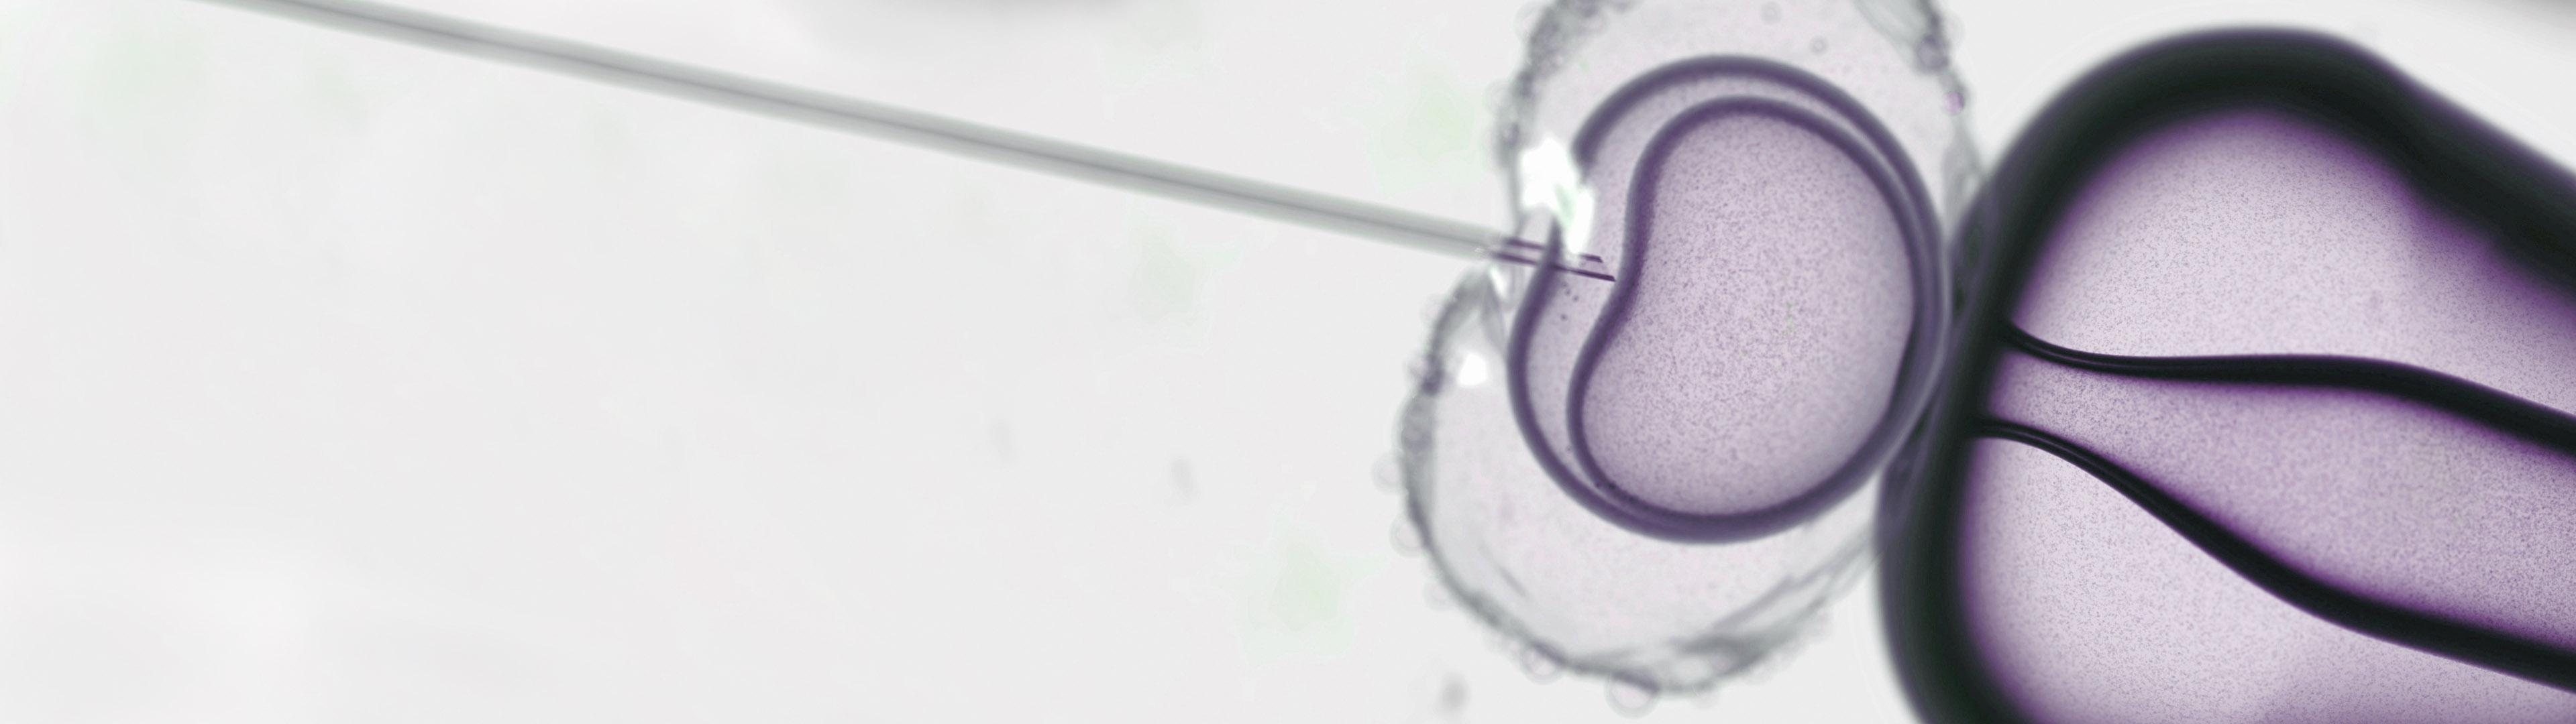

The key element of the IVF process involves the fertilization of the eggs “in vitro,” which simply means outside of the body. Eggs collected directly from the ovaries are combined with sperm in the laboratory to create embryos, which are then grown and nurtured in specialized incubators for three to five days before the best of the group is selected for transfer into the uterus, through the vagina and cervix.

- That same day, the eggs are fertilized with sperm in the laboratory and then placed in highly specialized incubators that carefully control their environment. The next morning, they are examined under a microscope to determine how many in the group fertilized successfully; on average 60-80% of the eggs that were fully mature can be expected to fertilize.